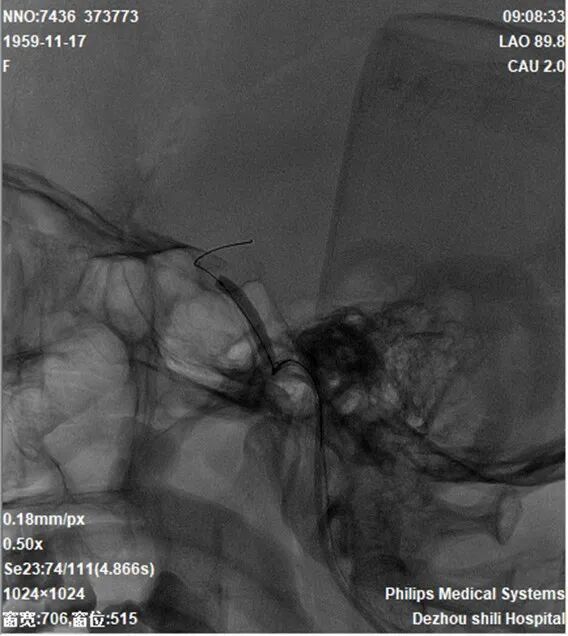

导引导管到位,导丝通过病变,球囊通过病变。

导丝怎么扩【载药时代 球扩天下】NOVA DES®颅内药物洗脱支架在颈内动脉颅内段重度狭窄的应用二例!_https://www.jmylbn.com_新闻资讯_第28张

球囊扩张过程。

导丝怎么扩【载药时代 球扩天下】NOVA DES®颅内药物洗脱支架在颈内动脉颅内段重度狭窄的应用二例!_https://www.jmylbn.com_新闻资讯_第29张